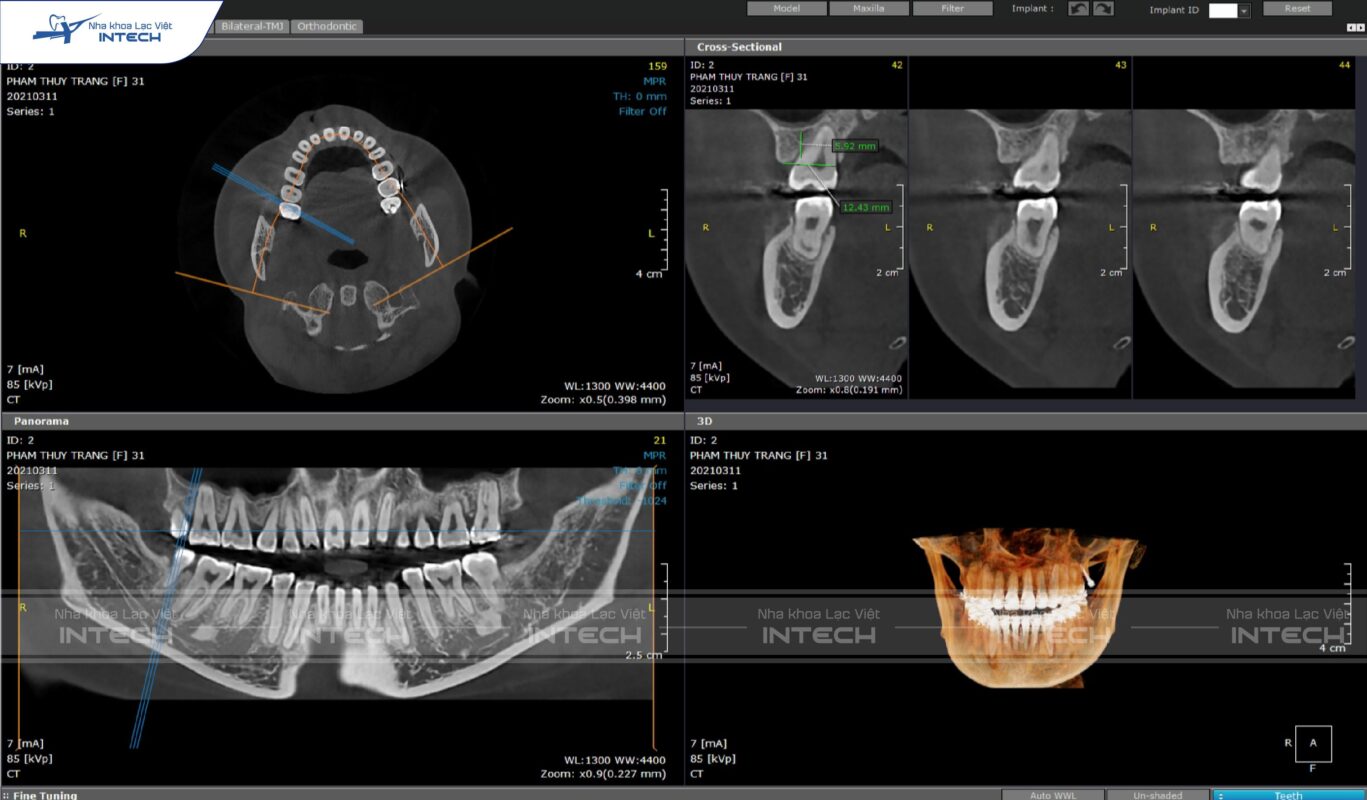

Phim CT Conebeam

Đây là phim cắt lớp và dựng hình 3D chuyên dụng trong Nha khoa nói chung và Chỉnh nha nói riêng. Các trường hợp răng ngầm, cấu trúc xương và thần kinh đặc biệt là những chỉ định chụp phim này.